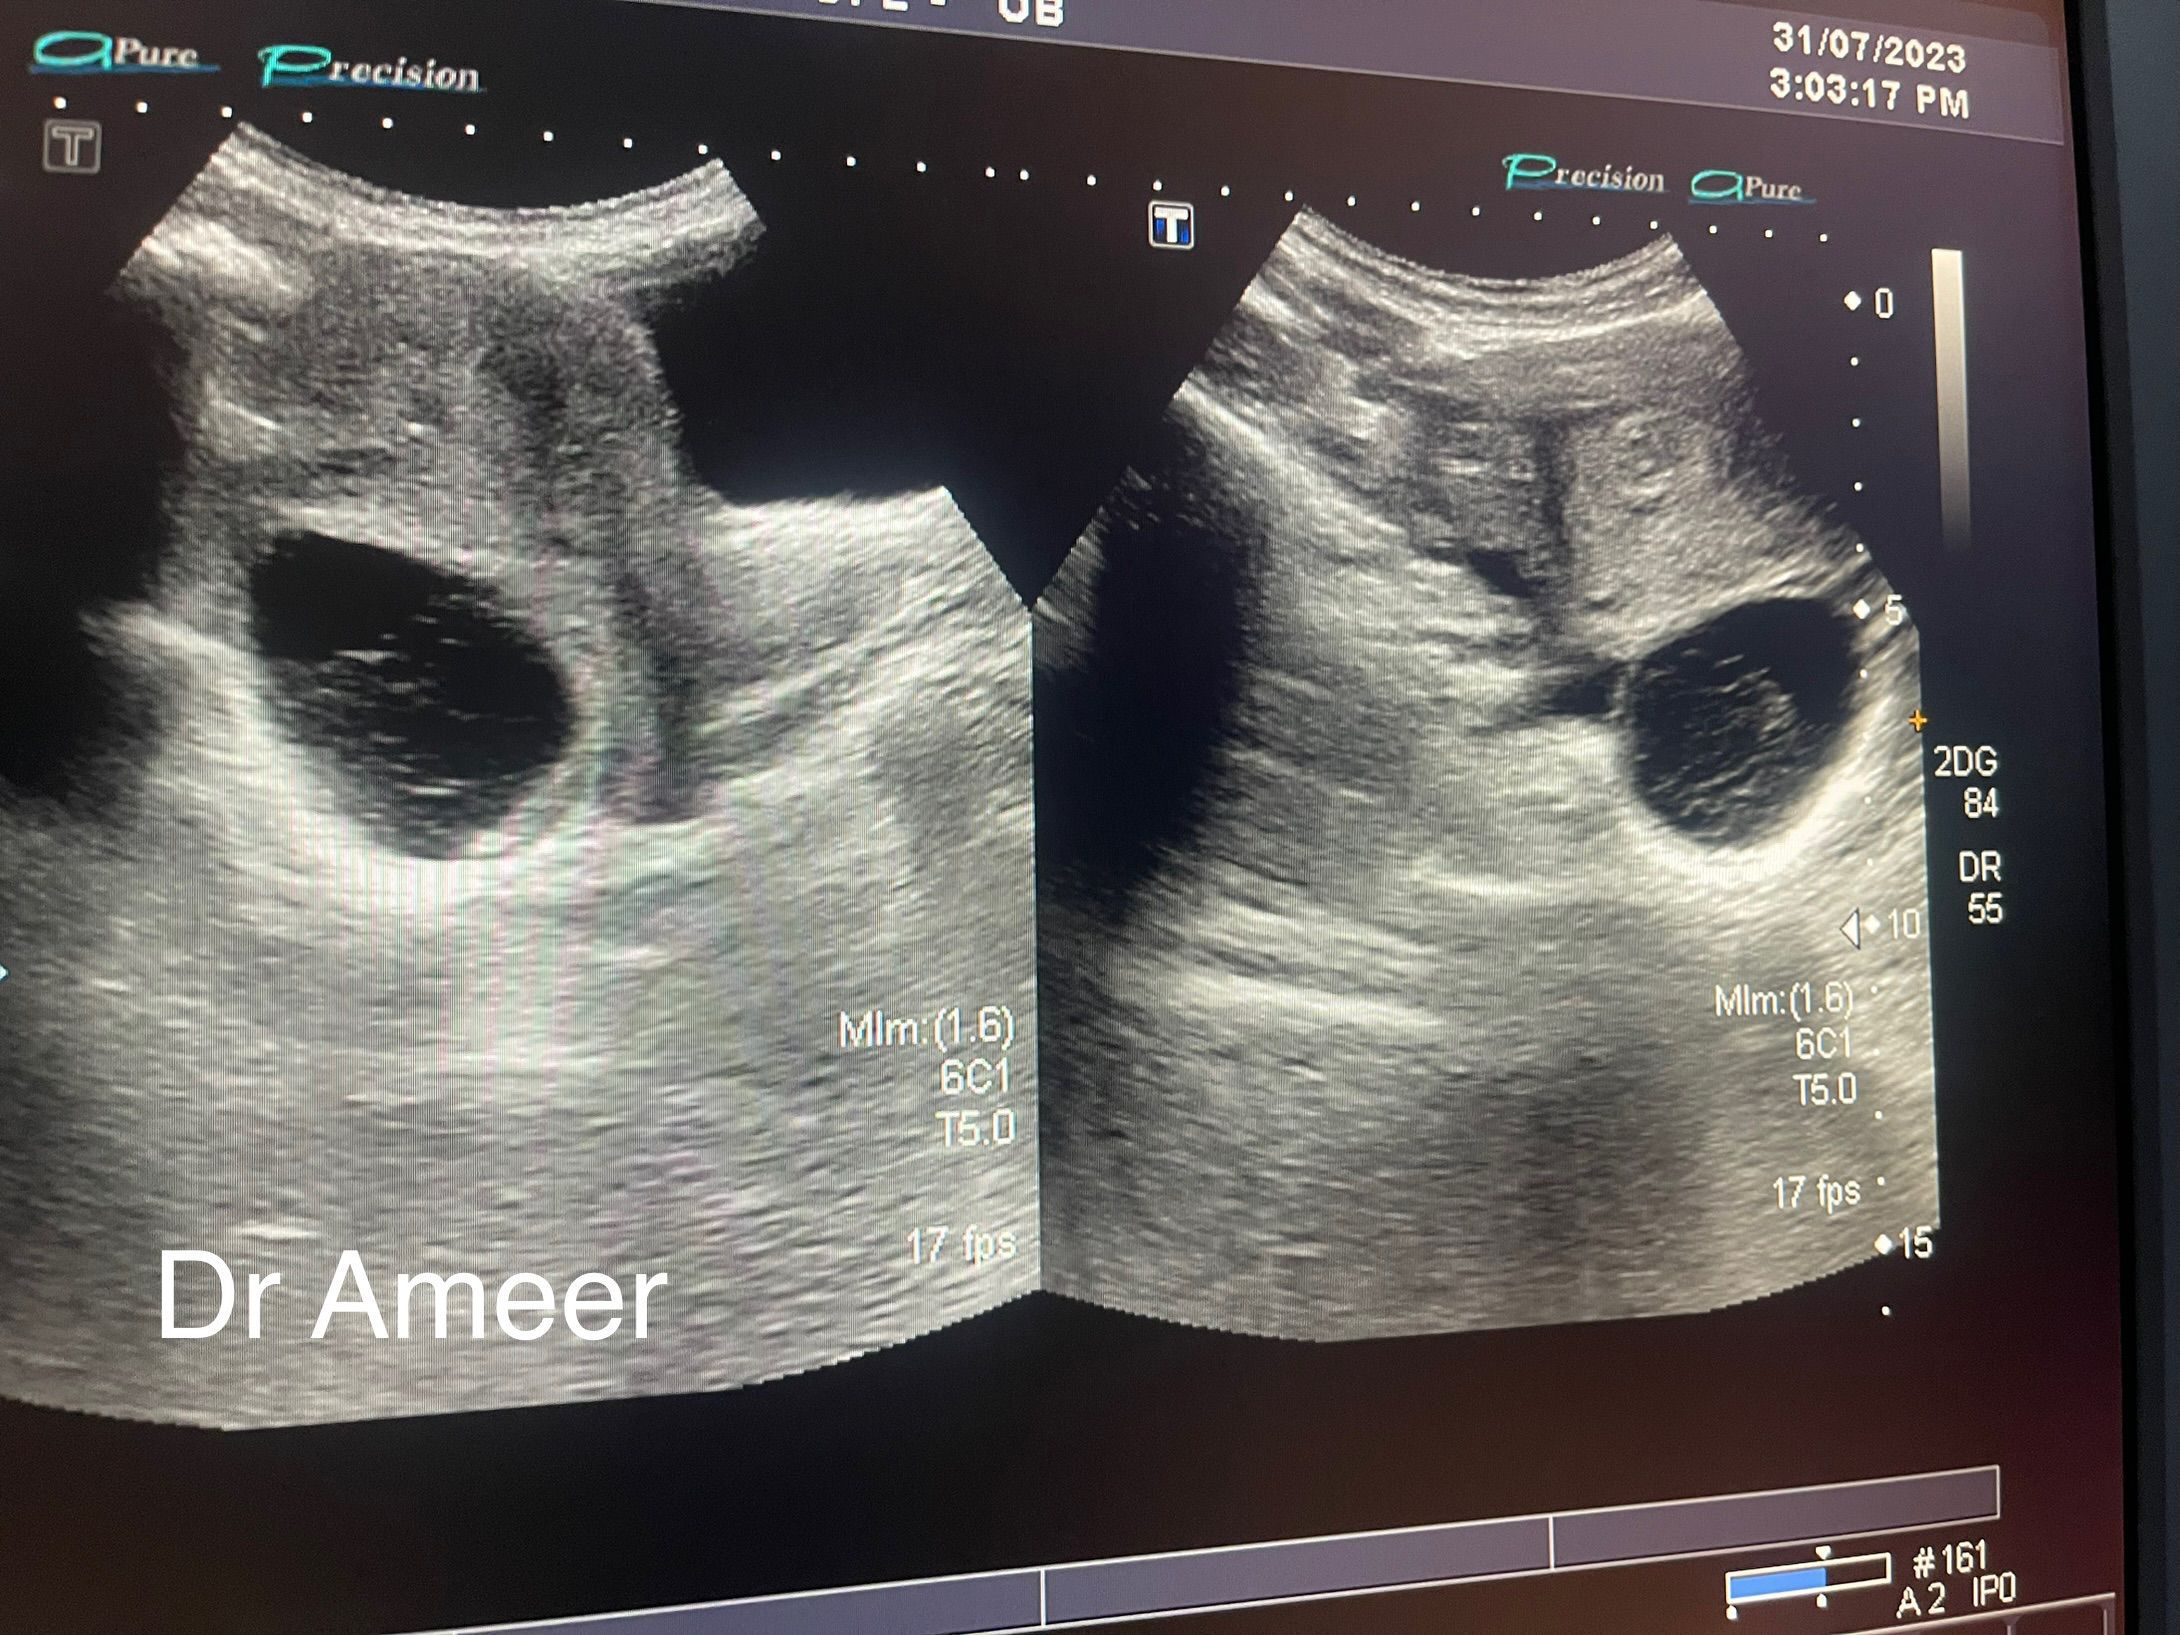

Can you appreciate a cyst?

25 years old Patient presented in Emergency with severe lower abdominal pain after examination and on ultrasound this image is appreciated.

Mostly hemorrhagic cyst